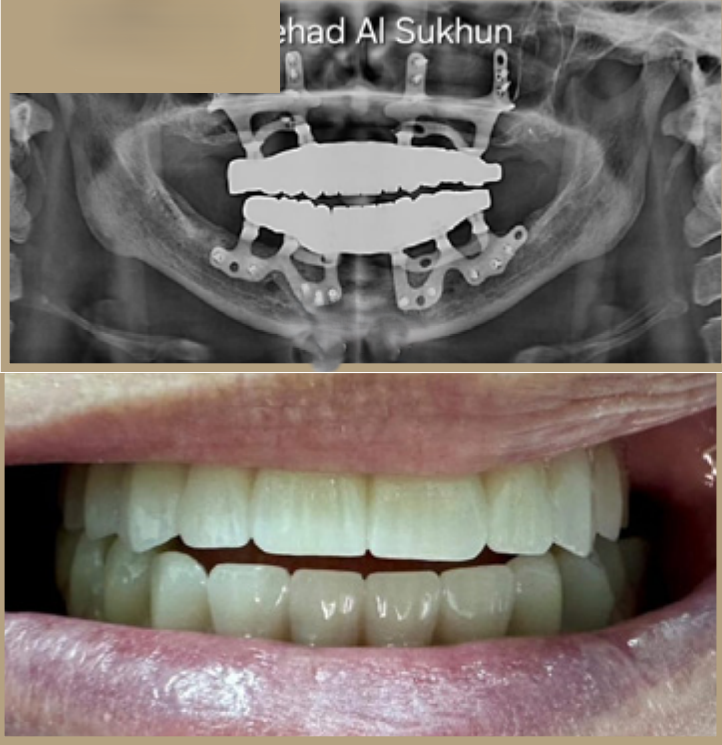

إذا كنت ترغب في الحصول على أسنان ولا تملك ما يكفي من العظام لإجراء علاج الزرع، لم يعد هناك حاجة إلى زراعة العظم من الآن فصاعدا.

تقدم زراعة الأسنان تحت السمحاق ثلاثية الأبعاد (3D subperiosteal implants) حلاً موثوقًا للحصول على أسنانك، خاصة في الحالات التي تكون فيها كمية العظام غير كافية لدعائم الزرع التقليدية.

عوده دون الحاجة إلى الخضوع لعلاج ترقيع عظمي واسع النطاق.

هذه التقنية ثورة في استبدال الأسنان!